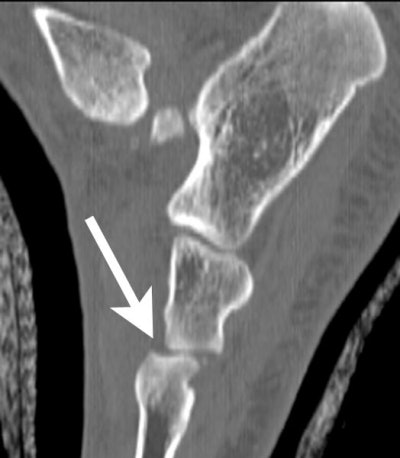

| Sagittal reformatted image through the medial aspect of the foot demonstrates the fracture (arrow) of the inferior portion of the navicular. |